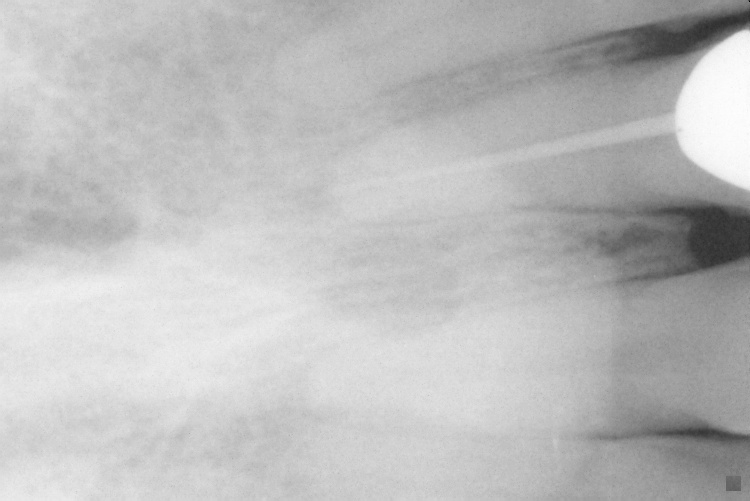

[PARENTDIR] Parent Directory - [IMG] IO000001.jpg 2020-07-28 14:17 77K [IMG] IO000002.jpg 2020-07-28 14:17 79K [IMG] IO000003.jpg 2020-07-28 14:17 82K